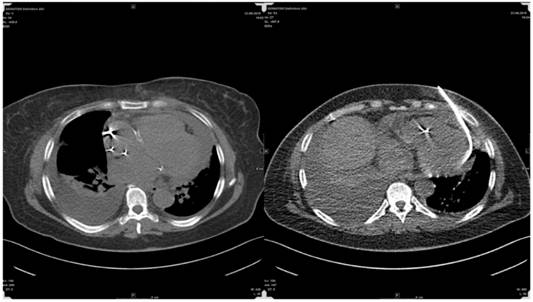

The research study was approved by our investigational review board (IRB) “G. Papanikolaou” General Hospital. We used a Fujinon, Olympus and Pentax linear endobronchial ultrasound system at different sites. The operators were Wolfgang Hohenforst-Schmidt (Fujinon system in Coburg Hospital, Olympus system in Fuerth Hospital) (Fig. 3.) and Paul Zarogoulidis (Pentax system in Thessaloniki) (Fig. 4.). Additionally, a cardiac ultrasound (U/S) system (Fig. 5-6.) and a C-Arm system were used (Fig. 7-8.). We used the cardiac U/S as an initial evaluation of the PE. Furthermore, its use offers the opportunity to evaluate real time changes of the cardiac hemodynamics due to reduction of PE while aspirating. During the procedure of aspiration, we used additionally a C-Arm system to present the location of the EBUS system within the thorax. The aspiration of PE has been previously proposed by the authors and with this research we applied the technique according to the approved protocol in a small number of patients with benign and malignant PE (Fig. 9-12.). 19 Ten patients were included in our study, three with benign and seven with malignant PEs. (TABLE 1.) The PE in all cases was sent for cytological evaluation (Fig. 13-14). The diagnosis was made upon this evaluation including the clinical setting.

The finding of a PE in patients with underlying malignancy creates a more complex dilemma, as not infrequently PE is due to alternative causes and not to direct neoplastic pericardial involvement. Posner et al.96 diagnosed in his series malignant pericardial disease in 18 (58%) of 31 patients with underlying cancer and pericarditis with pericardial effusion, while 32% of the patients had idiopathic pericarditis and 10% had radiation induced pericarditis. Porte et al. 97 studied 114 patients with recent or remote history of cancer and a PE of unknown origin requiring drainage for diagnostic or therapeutic purposes. Pericardioscopy was performed in 112 patients with pericardial fluid analysis and biopsy of abnormal structures or deposits under direct visual control. Malignant pericardial disease was found in 44 (38%) patients, while 70 (61%) patients had non-malignant pericardial effusions (idiopathic in 33 patients, radiation-induced in 20 patients, infectious effusion in 10 patients, and hemopericardium as a result of coagulation disorders in 8 patients). These studies show that, in more than half of the patients with underlying (present or recent even remote non-thoracical) cancer, a PE is due to causes different than direct neoplastic involvement. Therefore, the precise etiology of these PEs needs to be clarified due to obvious prognostic and therapeutic consequences. We believe that TPEA is a comparable easy and feasible method to perform such clarification especially in patients with actual or former malignant disease as we did in this series. Of importance is the fact that some oncological drugs may induce PE as well. Tyrosine kinase inhibitors often used in palliative situations in adenocarcinomas of the lung and doxorubicin can cause a special confusion in these patients as well.98 It has to be mentioned that beside interventional cardiologists and pulmonologists transthoracic approaches for PE are as well applied by interventional radiologists with high expertise: Following a personal note of Thomas Vogl the drainage of large PEs under CT-guidance is an easy, quick and safe approach. He reported about 150 drainages without any problems - yet approaching the pericardial sac antior.(Fig. 20) Another young field in interventional minimal-invasive medicine is epicardial ablation treatments for complex scars refractory to endocardial ablation (especially due to Chagas or ischemic heart disease) and various arrhythmogenic substrates by entering the ablation-catheters percutaneously into the pericardial sac.99-101 However this technique is not wide spread even in bigger Electrophysiology (EP) centres as the approach with a so called blind tap comprises a high risk of major complications including death up to 4-5% with a minor complication rate of 30% including pericarditis and PE.102,103 Delayed PE after endocardial ablation like in pulmonary vein isolation has occured.104,105 Interestingly recent experimental publications on an 'easy' approach for pulmonary vein isolation in atrial fibrillation consider transapical puncture of the left ventricle for retrograde transmitral access to the pulmonary veins.106

Radiologists' approach for pericardial effusion aspiration.